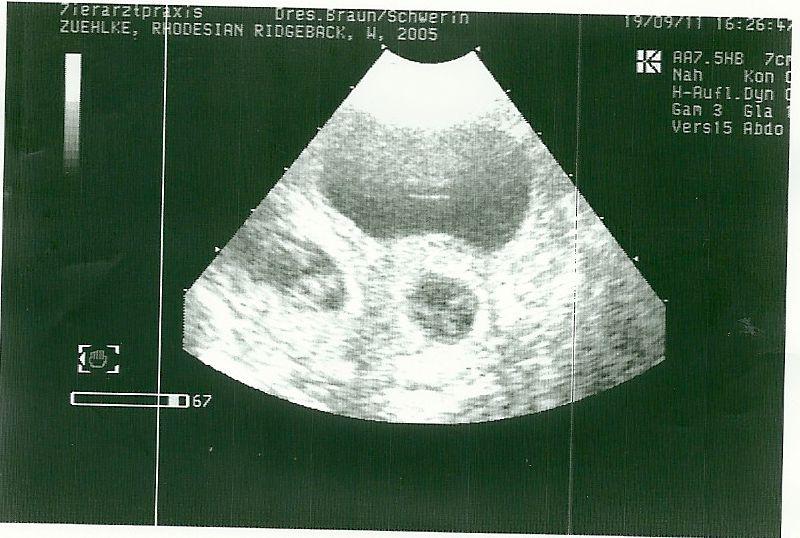

Zungwini Ife ist tragend. Karin Zühlke war mit ihr beim Ultraschall, der ein eindeutiges Ergebnis brachte.

Wir freuen uns sehr auf die Welpen, die um den 26. Oktober erwartet werden. Wer sich für einen Welpen aus dieser Verpaarung interessiert, kann sich an Frau Zühlke, Telefon 02763/214585 wenden.

Puppies will be born around october 26th. If you are interested in a puppy oft Zungwini Ife/ Bravo Topsecret Adhiambo, please contact Karin Zühlke, phone ++49/2763-214585.